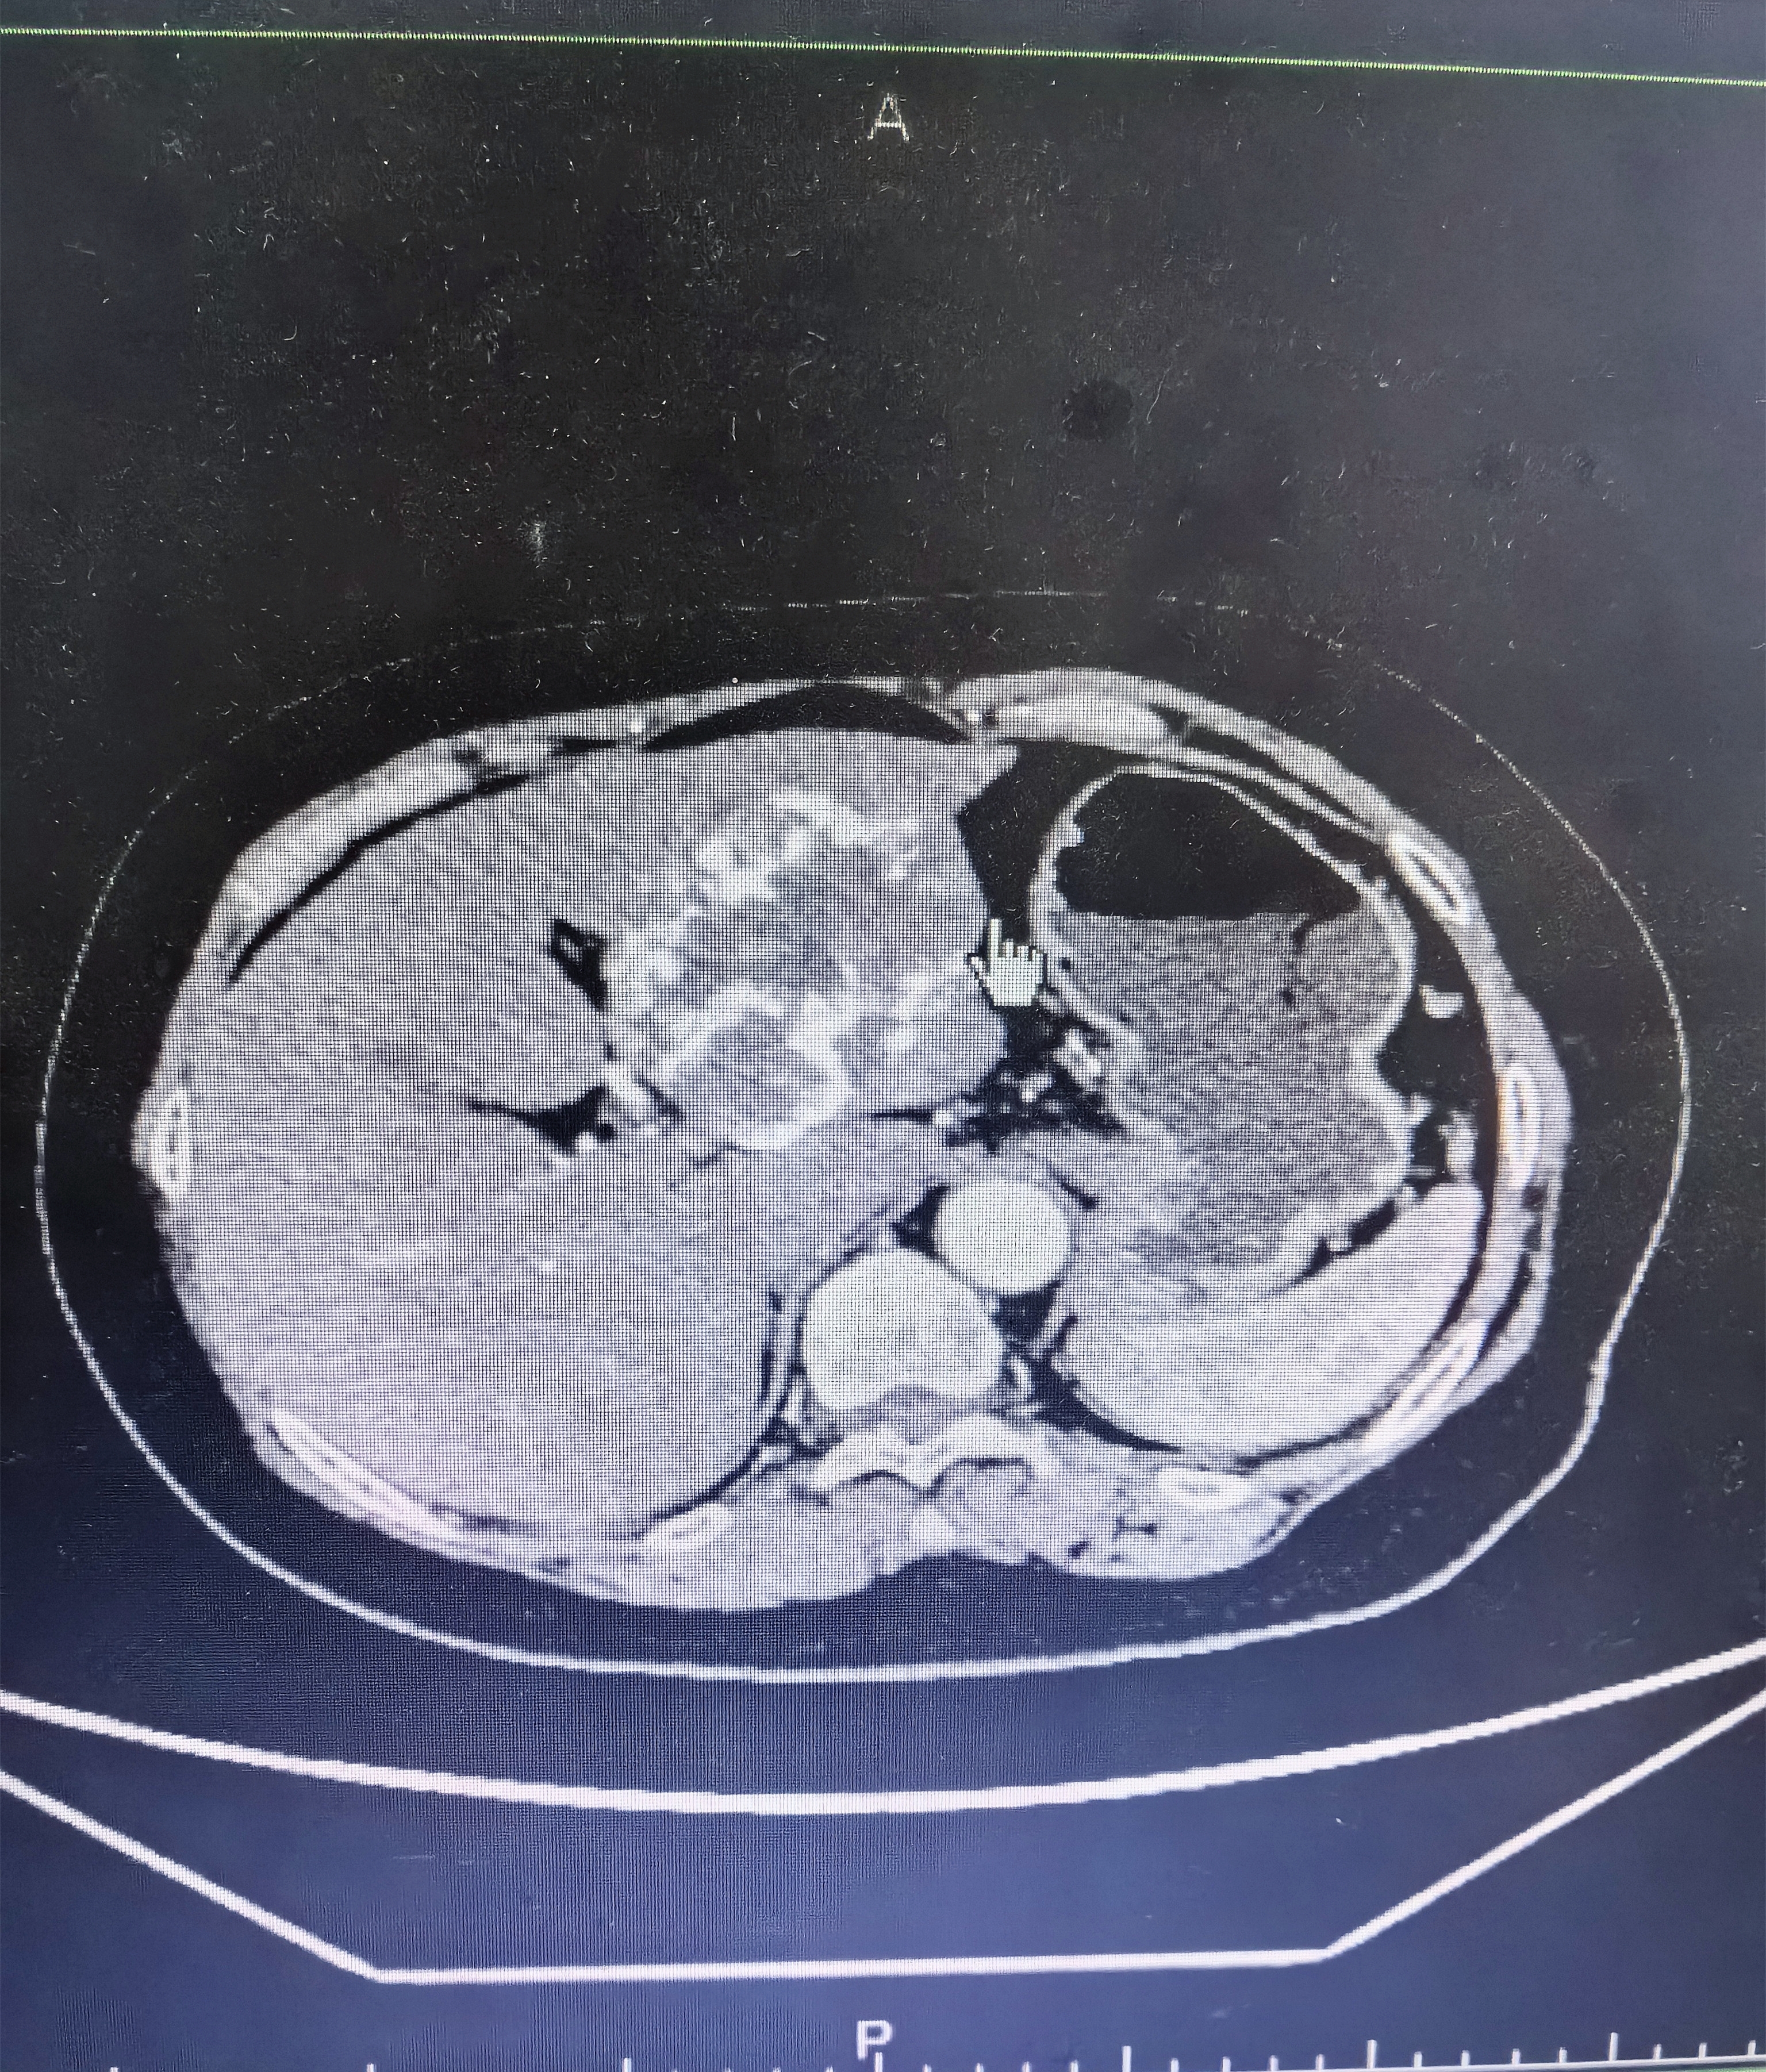

增强CT提示肝左叶2个血管瘤。

“徐奶奶的病情较为复杂,肝左叶存在两个血管瘤,其中一个直径接近8厘米。”该院肝胆外科主任邹卫华介绍道。考虑到徐奶奶年纪大、既往有高血压病史,且血管瘤肝内占位体积较大,为了积极应对术中可能发生大出血、胃肠穿孔、肠瘘等风险,邹主任第一时间与武汉协和医院顾劲扬教授取得联系,详细汇报老人病情并拟定施行“腹腔镜下肝部分切除术”的手术方案。